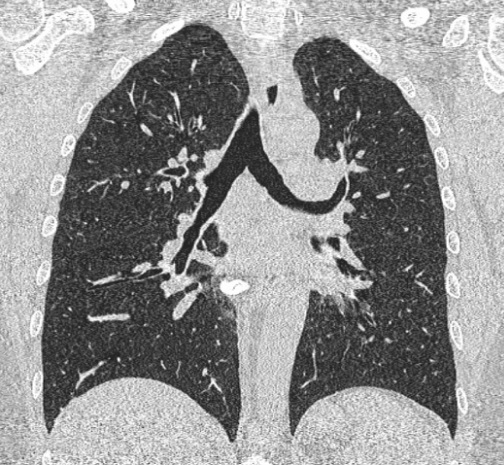

Même cas en fenêtre

parenchymateuse , coupe frontal La parenchyme

du poumon , artere, veine pulmonaire , trache et les

deux bronche hilaire etre en vue tres nette . Image

radiologique TDM en coupe coronal , fenêtre

parenchymateuse |